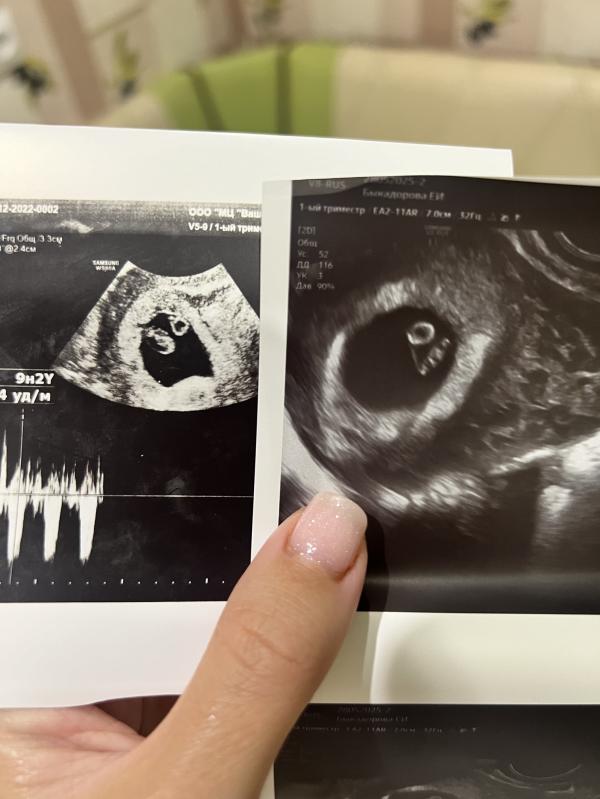

На втором фото слева сын в 7 нед , справа сегодняшнее )

По узи все замечательно. Сердечко бьется быстро 152 уд.мин.